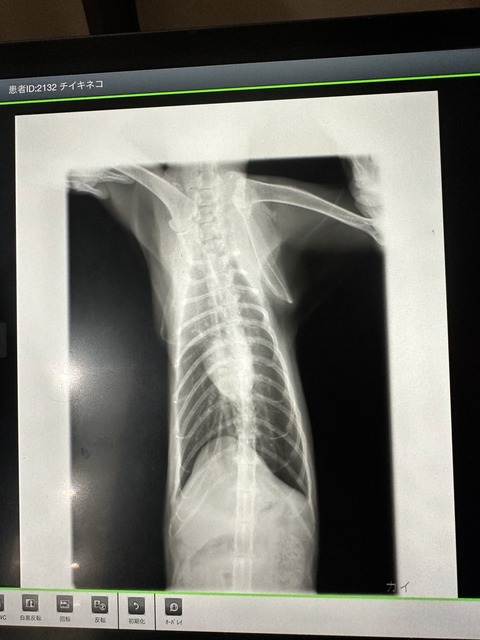

レントゲンも

相変わらず私が見てもあまりわかりませんが、

先生いわく問題なかったそうです